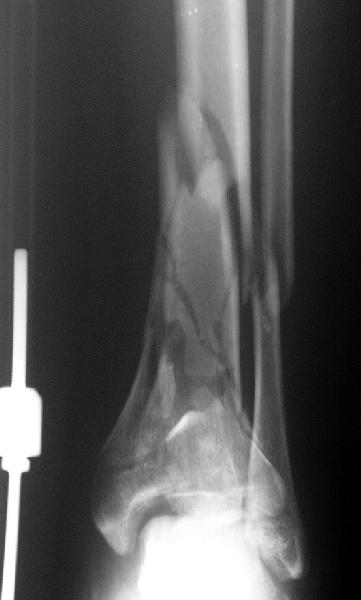

Re: Открытый оскольчатый внутрисуставной перелом дистального отдела большеберцовой кости

Отправитель: Кучерявый Игорь 18 Март 2006, 21:03

А была ли необходимость менять аппарат на такую пластину? Выигрываем в возможности более ранней разработки голеностопного сустава?

Пластинка красивая. Чуть только спереди назад идет, не сосем по оси большеберцовой кости. А там не маловато фиксаторов собственно в дистальном суставном конце кости? А вправляли его как? Как будто или осталось запрокидывание кзади или недонизведен передний край. Но с учетом исходного тяжелейшего повреждения - все равно здорово.